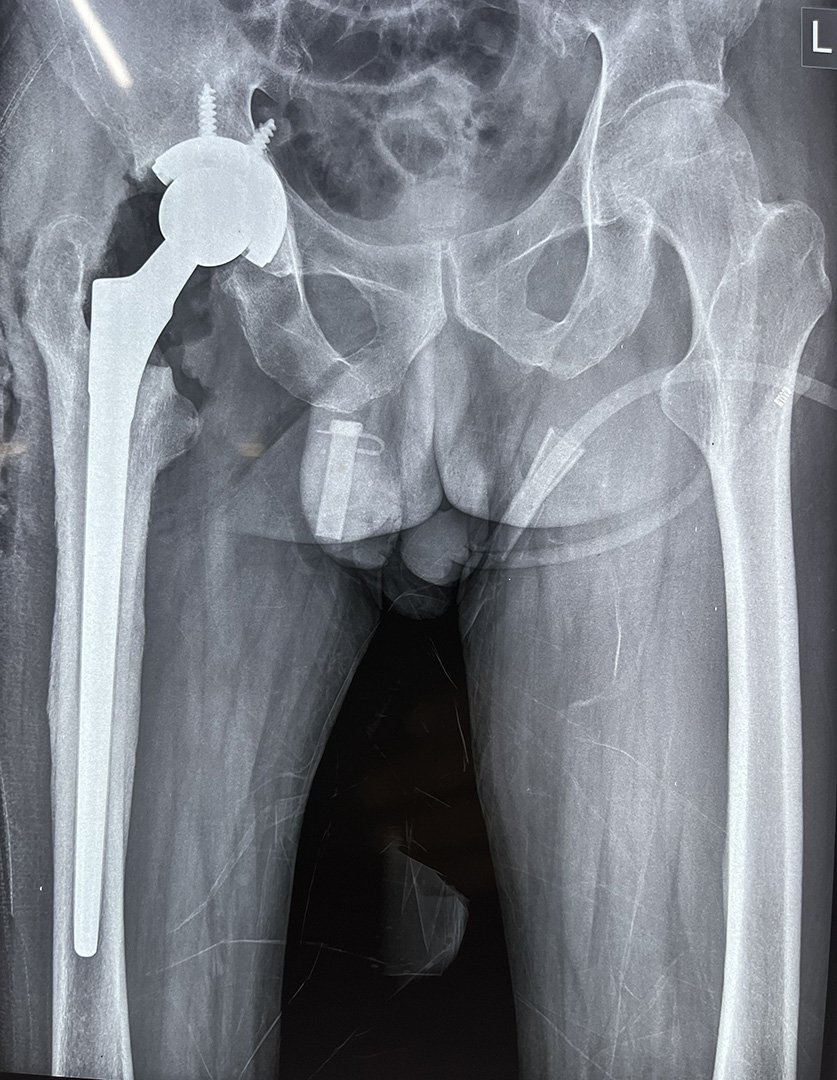

Post-Op -Stage 1 Cement Spacer